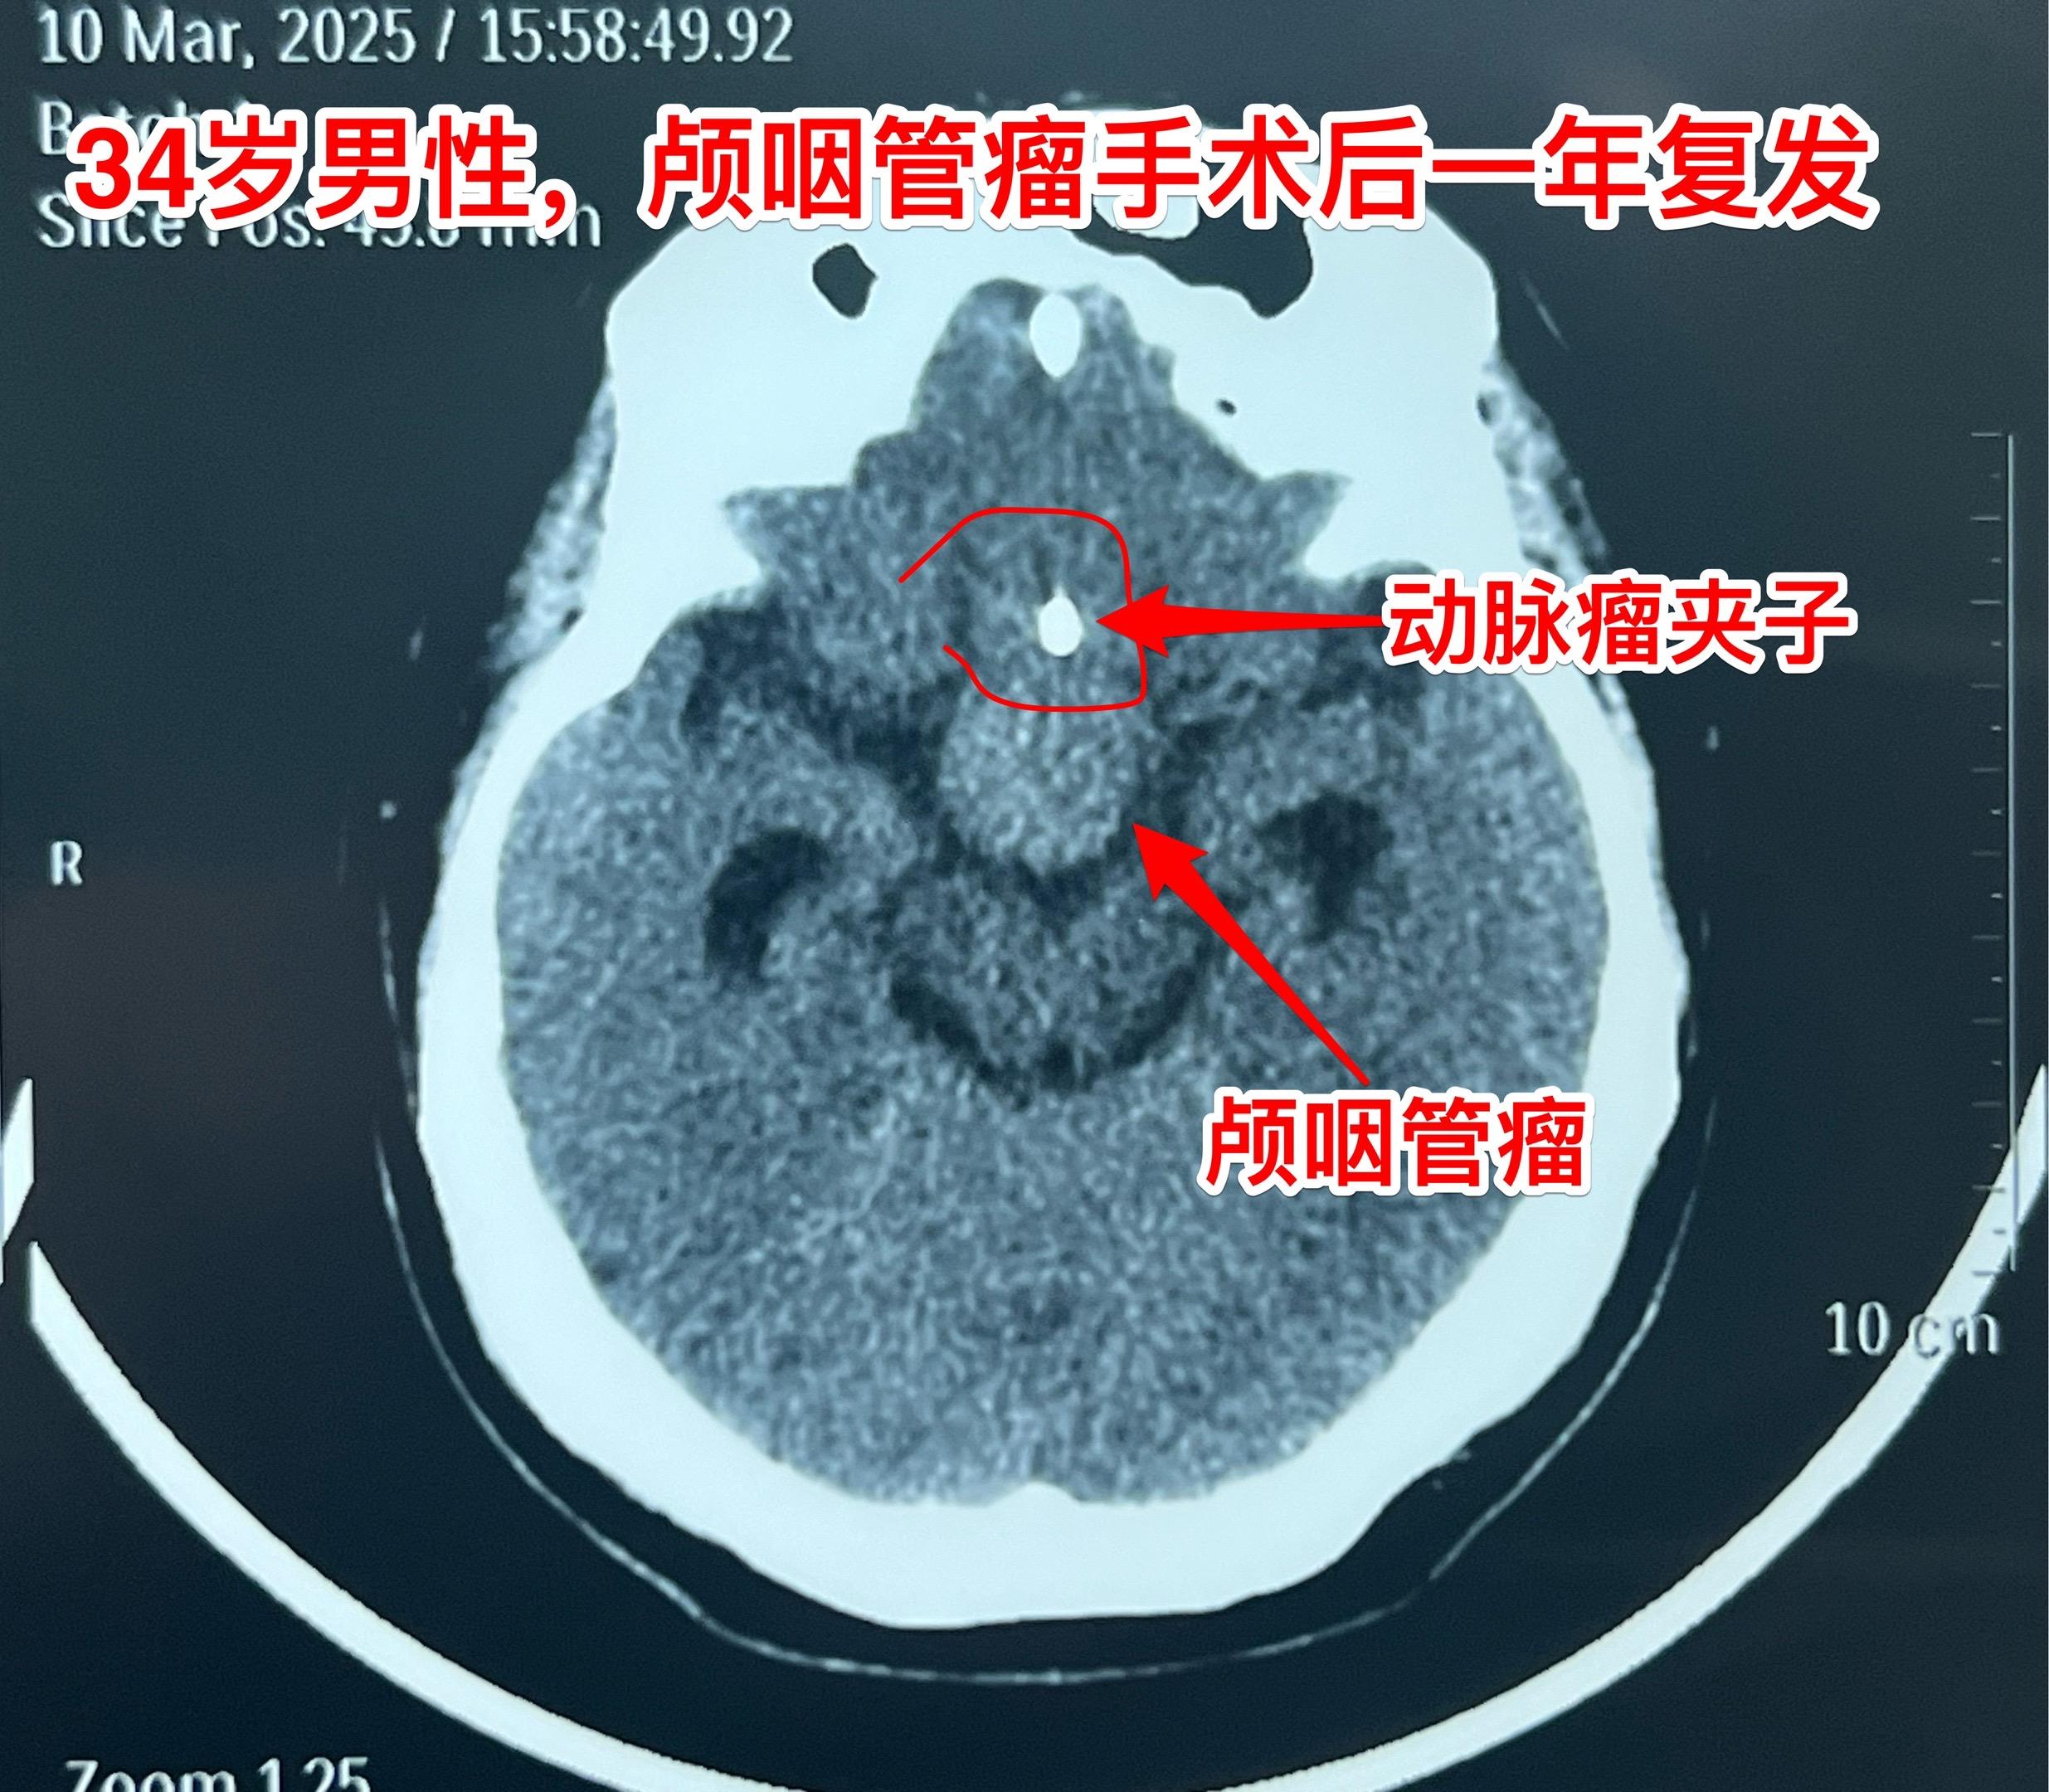

乳头型和造釉型颅咽管瘤的混合型存在吗?34岁男性,广东省惠州市人。一年前因视力下降发现颅咽管瘤,在广东省某医院行开颅手术切除一部分肿瘤。肿瘤复发了来三博脑科医院找我治疗。 第一次手术后病理报告考虑是乳头型颅咽管瘤和造釉型颅咽管瘤的混合型(太罕见了)。手术中还留置了一个动脉瘤夹子、一个Ommaya囊。 昨日作了开颅手术,术中看见肿瘤血供十分丰富,和第三脑室壁及大脑后动脉粘连。手术经历9.5个小时,肿瘤得到完全切除。术后病人的精神状态及四肢活动均很好。希望以后肿瘤不复发。等待病理